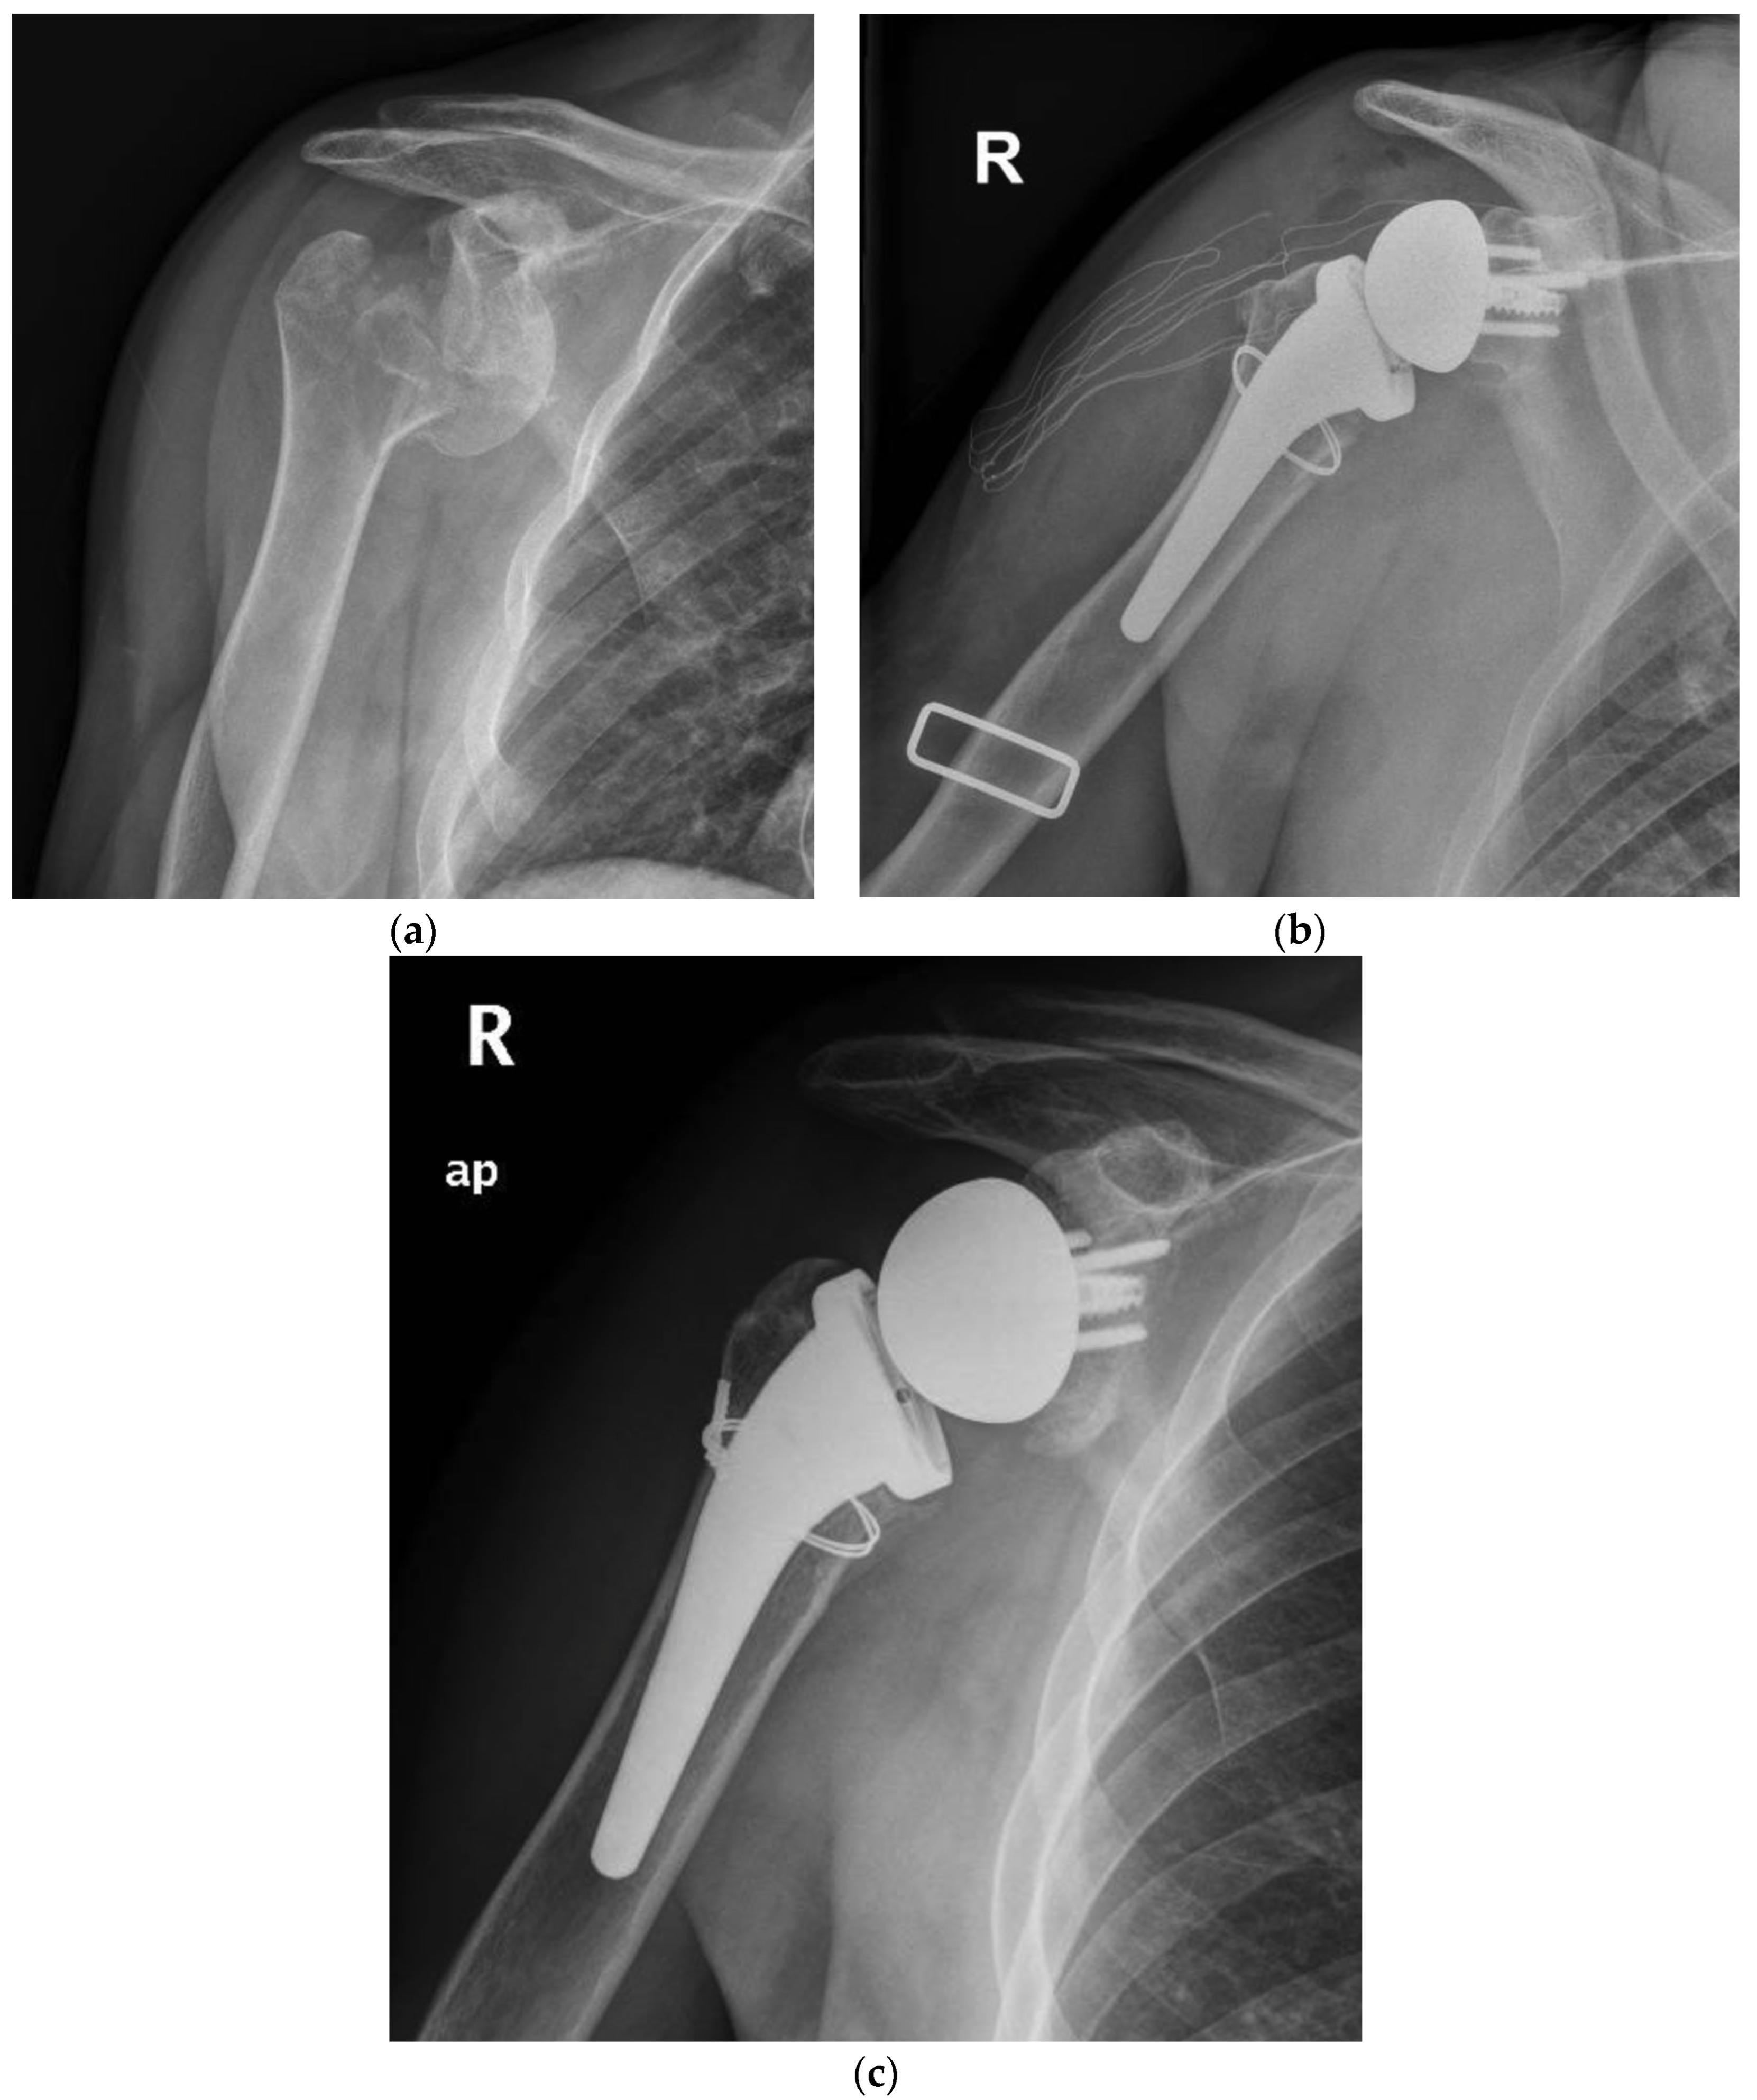

Figure 2.

(a) Preoperative radiographic image of right shoulder showing acute (Neer four-part) proximal humeral fracture with calcar fragment. (b) Immediate postoperative film of right shoulder showing calcar fragment fixation with steel wire cerclage. (c) 5.5 years postoperative film of right shoulder showing healed tuberosity and medial calcar.

At radiographic evaluation, 58 of 68 (85%) of the greater tuberosities demonstrated osseous healing (Figure 1 and Figure 2) without a significant difference observed between the two groups. A statistically significant difference was found indeed focusing on the influence of tuberosity healing on the clinical outcomes regardless of medial calcar fracture extension. The subgroup of patients with tuberosity healing achieved significant higher ASES scores and active external rotation than those without tuberosity healing (mean ASES score of 92 and 82, respectively, p < 0.05; mean active external rotation ER1 of 45° and 22°, respectively, p < 0.05).

The experience of cementless fixation thus far published has regarded mainly three-, four-, and rarely two-parts PHFs. No mention may be found on more severe fracture patterns, such as those with a medial calcar fragment [23]. Moreover, most of the series have employed standard or long stems with a press-fit achieved often in the diaphyseal bone. Our series supports the safety and viability of RTSA with a cementless and metaphyseal stem’s fixation for two-, three-, and four-part PHFs but as well in selected fractures with a calcar fragment that is sizable to be fixed with steel wire cerclage (Figure 1 and Figure 2). At a minimum follow-up of five years, the clinical outcomes (ASES score of 89.2, Simple Shoulder Test score 91.1 and NRS pain of 0.8) were satisfactory and supported by the comparison with a control group of patients without the calcar fragment (ASES score of 91.6, Simple Shoulder Test score 90.4 and NRS pain of 0.5). For both groups, the results are likewise comparable to those achieved by other series with either cementless or cemented stems.